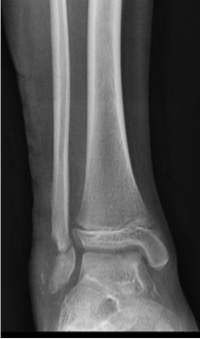

IntroducciónLas fracturas Salter-Harris VI (SHVI) son lesiones que se caracterizan por presentar ablación del anillo pericondral. Son infrecuentes en niños pero potencialmente devastadoras. El objetivo de este estudio fue evaluar el mecanismo de producción, el tratamiento y los resultados funcionales de estas lesiones localizadas en el pie y el tobillo.Material y métodosSe analizaron retrospectivamente todos los pacientes con lesiones SHVI de tobillo y pie tratadas entre Enero de 2010 y Enero de 2013. Se documentaron datos demográficos, clasificación, mecanismo de lesión, tipo de lesiones asociadas y número de cirugías que requirieron. Los pacientes fueron evaluados funcionalmente con el score de AOFAS y radiográficamente para determinar la viabilidad de la fisis, acortamiento del miembro o deformidad angular.ResultadosSe analizaron 5 fracturas en 4 pacientes (3 masculinos y 1 femenino). La edad promedio al momento de la lesión fue de 7.5 años (rango, 6 a 10 años). El seguimiento promedio fue de 26.2 meses (rango, 12 - 37 meses). De acuerdo a la subclasificación de Peterson 3 pertenecían al grupo A, 1 al B y 1 al C. 3 lesiones se produjeron como consecuencia de accidentes de moto y 2 por auto versus peatón. Todos los casos se acompañaron de pérdida de sustancia, el 75% presentaba lesiones en más de un hueso y el 50% lesiones tendinosas asociadas. Cada paciente requirió un promedio de 3.2 cirugías (rango, 2 a 5). El score AOFAS promedio fue de 79.8 puntos (rango, 62 – 100 puntos). Radiográficamente, solo el 40% de las fisis afectadas permanecían viables al último control.ConclusiónLas fracturas SHVI se acompañan de una gran variedad de lesiones asociadas, requieren múltiples cirugías y suelen producir un cierre precoz de la fisis y algún grado de discapacidad. Se requieren medidas de prevención para evitar la exposición de los niños a este tipo de lesiones. El tratamiento temprano es fundamental para prevenir el desarrollo de deformidades.Descargas